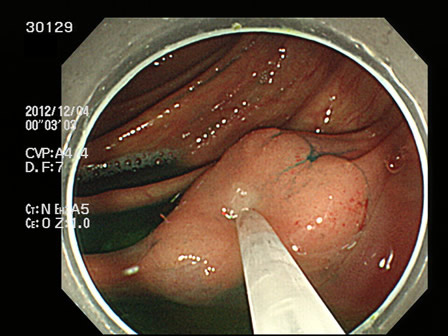

上記100名より抽出した平坦・陥凹型腺腫(=癌化の危険が高いが見落としやすい病変)の内視鏡写真